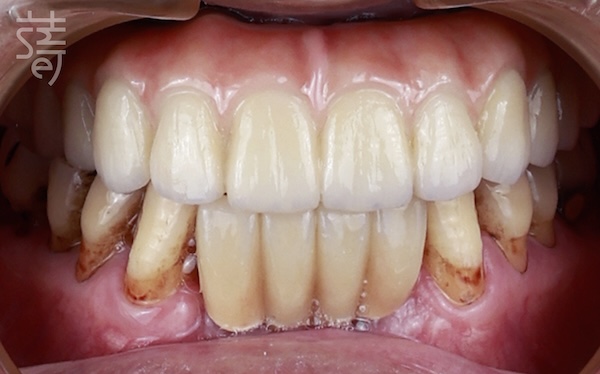

蒔美All-on-5 超越耐用,更締造極致美學

Beyond Function: Smile’s All-on-5 as a Work of Aesthetics

許多人以為 All-on-5 只是一場功能性的重建,

但All-on-5也可以是美學實踐。

在蒔美,我們更進一步放眼笑容的美學價值。

Many think of All-on-5 purely as functional reconstruction. At Smile, it is also an act of aesthetics.

透過DSD微笑設計與Rayface臉部掃描,

蒔美精細描繪出最自然和諧的微笑曲線,

讓修復不僅實用,更能展現個人特質。

不同於傳統一體成型假牙,搭配全瓷獨立牙橋,

日後若需維修或局部更換更加便利,

確保笑容在舒適與美觀之間持續長久。

Through DSD smile design and Rayface facial scanning, the clinic crafted a smile line that looked natural and harmonious, tailored to his features. Instead of monolithic dentures, they used individual porcelain bridges, which can be easily repaired or replaced over time—ensuring beauty and practicality endure together.